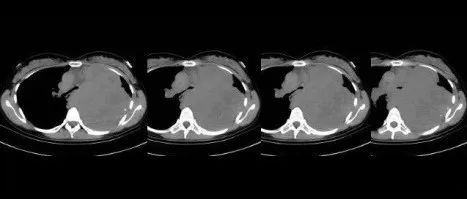

医学影像  yxyx-app  医学影像APP,打造伴随医生快速成长的影像学习社区。与影像园(Xctmr.com)一起提供最全面的影像案例库、基础(解剖、病理、影像诊断)知识、影像技术及考题等,为医生提供最佳的医学影像参考。【所属科室】呼吸科【基本资料】患者,女,26岁【主诉】胸痛半天【影像图片】【讨论问题】如何诊断?【医学影像APP用户讨论】评论:左肺上叶占位,肿块基底部位于后纵隔内,增强后不均匀强化,左肺上叶支气管受压狭窄、伴肺不张,考虑神经鞘瘤可能。...